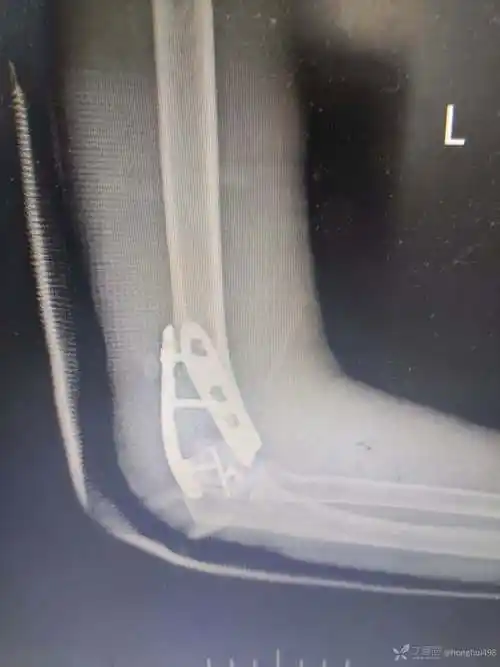

如此严重的肱骨远端粉碎骨折,还能治好吗?

成人肱骨远端骨折分为高能量损伤骨折和低能量损伤骨折.

肱骨远端单柱骨折分类与治疗提示